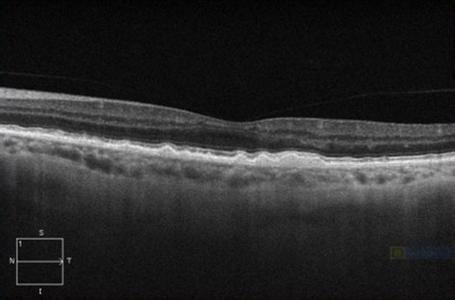

老年性黄斑变性OCT

老年性黄斑变性OCT,湿性老年黄斑变性oct

萎缩型老年性黄斑变性玻璃膜疣的频域光相干断层扫描图像特征

湿性老年黄斑变性oct

老年性黄斑变性oct图片

黄斑变性oct

干性黄斑变性oct图片

黄斑变性oct图片

黄斑变性OCT读图